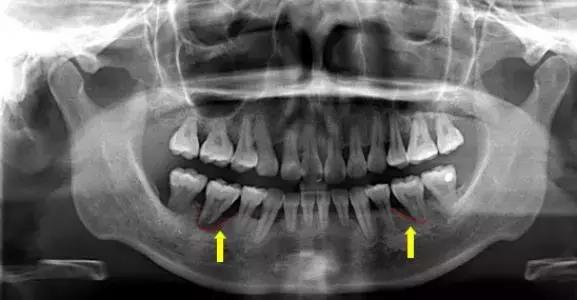

三.牙齿松动或脱落由于牙周组织被破坏,特别是牙槽骨吸收加重时,支持牙齿力量不足,出现牙齿松动、移位等现象。此时常伴有牙痛,牙龈慢性出血及口臭加重现象。